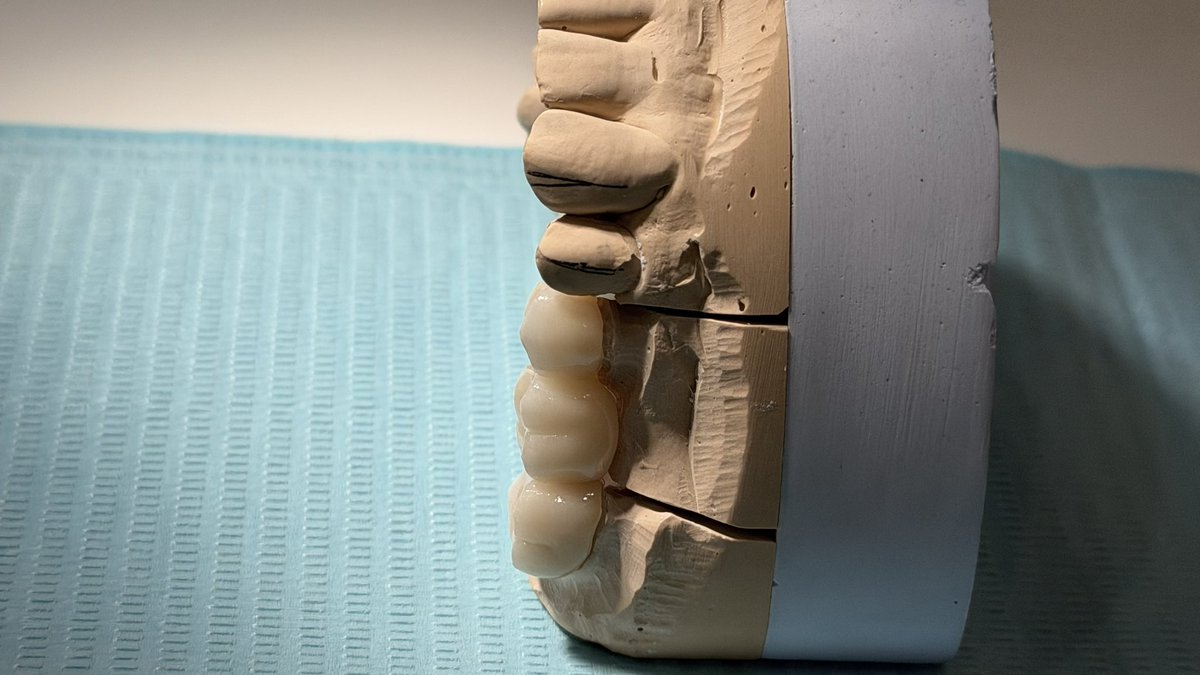

Today’s case✨: Replacement of missing #26 was accomplished using a zirconia fixed bridge (Shade B2). Tooth #27, previously endodontically treated, was reinforced with a fiber post and core build-up. Ensuring functional stability and optimal esthetics.